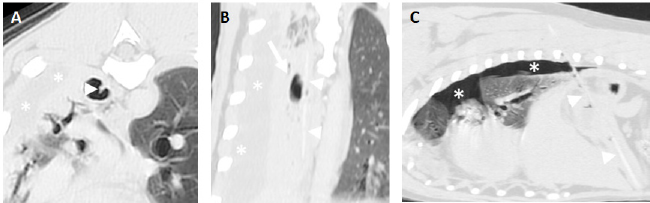

Fig. 1. Examples of fragments of wooden skewer perforating a jejunal loop. A and B. Parasagittal pre (A) and postcontrast (B) images (level 40 HU, width 250 HU) of the same patient with a fragmented wooden skewer (arrowheads) perforating the jejunum in the caudal abdomen with the ending tip penetrating the right psoas muscles. In the pre-contrast images, the portion of the foreign body embedded in the soft tissues is better visualized than in the post-contrast images, while the soft tissue abscessation is better depicted in the latter (arrows). C. Transverse post-contrast CT image (level 40 HU, width 250 HU) of another patient showing a hypoattenuating fragmented wooden skewer foreign body (arrowhead) penetrating a jejunal loop in the cranial abdomen. A marked peritoneal fat stranding is seen surrounding the small bowel loop and foreign body (arrows).

It has been previously speculated that the length and rigidity of this type of wooden foreign bodies prevent them from passing into the body or antrum of the stomach and cause them to perforate the wall of the fundus (Penninck and Mitchell, 2003). Accordingly, all the largest foreign bodies had one of the tips lodged in the stomach and longer perforating trajectories that extended either into the thorax or paravertebral/costal soft tissues depending on the orientation. The remaining and shorter foreign bodies were more prone to advance into distal portions of the gastrointestinal tract causing perforating lesions in the jejunum (Fig. 1). However, one of these smaller wooden foreign bodies was within a right caudal lung lobe and a clear communication with the abdomen was not seen on CT images. An origin from the digestive system, either the oesophagus or the stomach, was suspected as there was no previous history or secondary lesions supporting a theoretical inhalation or penetrating trajectory from the thoracic wall. Interestingly, this patient had a previous history of resolved abdominal effusion which could potentially be explained if a migrating pathway from the gastrointestinal tract was followed by the fragmented wooden skewer.